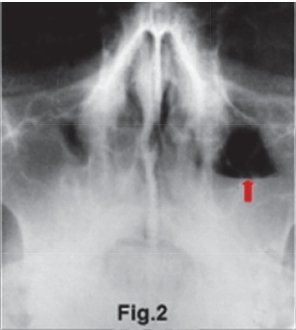

The intra-oral radiograph (Fig.1) shows a lesion at the apex of the 18. The lesion has extended to destroy a portion of the antral floor. There is also loss of the lamina dura and the presence of a "halo" (green arrow) of periosteal new bone suggestive of an osteitis. Some authors refer to this lesion as a localized mucositis or sinusitis of the left maxillary sinus. A Water's view of another patient (Fig. 2) shows an opaque right maxillary sinus and a classic air-fluid level (red arrow) in the left sinus, features which are consistent with acute sinusitis. Another example of acute sinusitis is discernible on the axial CT (Fig. 3) scan of another patient showing a clearly opacified left maxillary sinus with mucosal thickening and an air-fluid level (red arrow). Acute sinusitis presents clinically with facial pain, headaches, local tenderness and purulent discharge and is a common infection of the maxillary sinuses. Figure 4 is a Water's view of the maxillary sinuses showing a very sclerotic right sinus and small sclerotic maxillary antra in the left sinus (purple arrows), which is suggestive of chronic sinusitis. An axial CT scan (Fig. 5) of the same patient shows marked thickening of the walls of the right maxillary sinus with a thickened mucosa. The medial wall defects indicate that prior nasal antrostomies had been performed (blue arrow).